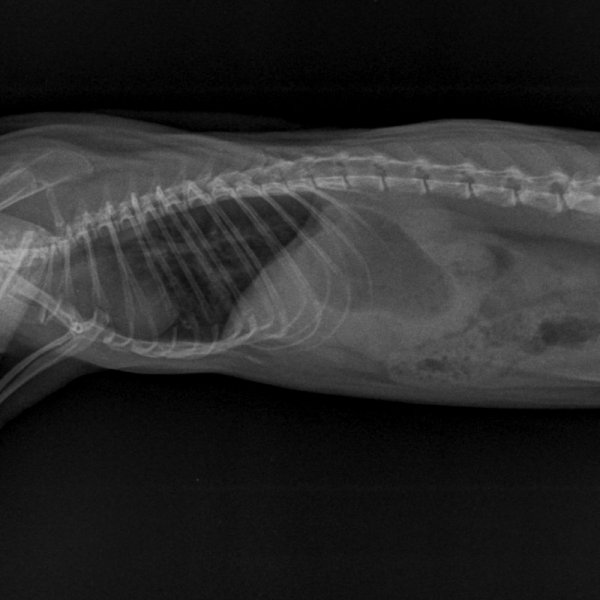

Fin mars j'ai trouvé la respiration de Kobayashi Maru étrange. Elle était un peu plus rapide et superficielle. Dans le doute, j'ai pris RDV pour une radio lundi 4.

Le WE juste avant, il a commencé à faire de légers bruits respiratoire, et sa respiration est devenue clairement plus rapide. À la pesée, je me suis aperçue qu'il avait de nouveau perdu du poids (390g).

À la radio, pour reprendre Artefact "c'est pas si pire", mais ça pourrait être mieux. On trouve quelques foyers. On part avec le véto sur 10 jours de doxycycline, 5mg/kg/12h, en PO.

Les radios d'hier :

NAC-THORAX PROFIL-04_04_2022-14_56_20-547.JPEG

NAC-ABDOMEN FACE NORMAL-04_04_2022-14_56_20-157.JPEG